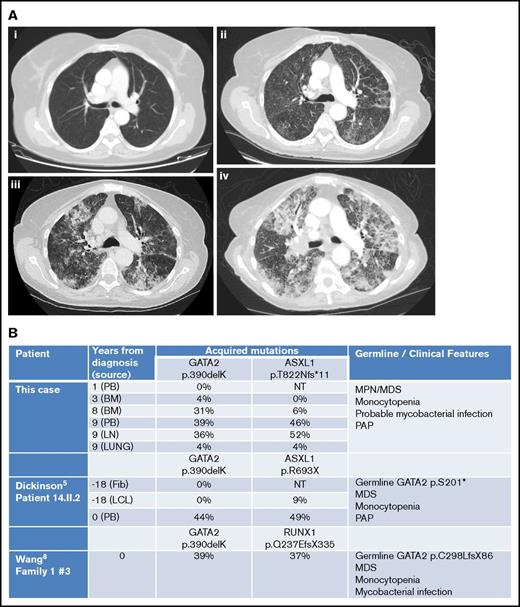

Imaging and molecular investigations. (A) Serial computed tomography chest images (2007-2015). (i) June 2007: no respiratory symptoms. Normal imaging. (ii) January 2015: no respiratory symptoms but evidence of progressive MPN/MDS. Early interstitial changes are present. (iii) June 2015: cough and breathlessness. Progressive interstitial changes plus air space shadowing are present. (iv) September 2015: respiratory failure secondary to PAP. “Crazy paving” changes plus consolidation characteristic of PAP visible. (B) Comparison of somatically acquired c.1168_1170delAAG p.390delK GATA2 mutations. Three patients have been reported with somatically acquired p.390delK mutation in GATA2. Germ line mutations in GATA2 and other cooperating mutations in ASXL1 or RUNX1 were also present in two previous cases. Fib, fibroblast; LCL, lymphoid cell line; LN, lymph node; NT, not tested; PB, peripheral blood.

However, by then, she reported weight loss, worsening cough with breathlessness, and dystrophic nails consistent with fungal infection. Chest computed tomography revealed progressive changes with interstitial thickening and air space shadowing throughout both lungs, plus small volume necrotic mediastinal lymphadenopathy (Figure 2A). Sputum, BAL, and endobronchial ultrasound biopsies of her central lymphadenopathy were culture negative; lymph node histology showed acute necrotic changes. BAL contained branching hyphae consistent with Aspergillus species. BAL galactomannan was positive at 1.58, and voriconazole was commenced.

Repeat BM biopsy showed myelofibrosis with hypolobated nuclei and 5% to 10% blasts. Hydroxycarbamide was substituted for ruxolitinib; her pulmonary symptoms worsened despite anti-infective treatment, and a thoracoscopic surgical biopsy of the lung confirmed a diagnosis of PAP. Anti–GM-CSF antibodies were negative. Her symptoms and radiology progressed in line with PAP, and she died in September 2015 of respiratory failure.

She was investigated for the presence of GATA2 mutation. BM DNA was extracted from paraffin blocks using the QIAamp DNA FFPE Tissue Kit (56404; QIAGEN) according to the manufacturer’s instructions. Using Sanger sequencing, the patient was found to harbor a mutation in exon 8 of GATA2 (c.1168_1170delAAG; p.390delK) and a mutation of ASXL1 (c.2464_2465insA; p.T822Nfs*11). The GATA2 mutation was predicted to be disease-causing using the MutationTaster prediction program6 (Mutation Surveyor software version 4.0.8). On retrospective analysis of her previous DNA samples and estimation of variant allele frequency from electrophoretograms, this GATA2 mutation was not detected in 2006, increased in abundance from 2009 to 2015, and was only found at 4% in lung tissue in 2015, suggesting that it was an acquired somatic mutation (Figure 2B; supplemental Figures). ASXL1 mutation was observed emerging at later time points, probably as a subclone.

In summary, we present details of an adult with MPN/MDS evolving to myelofibrosis over 7 years. She acquired a somatic GATA2 mutation 3 years after initial diagnosis. Three years later, she developed possible mycobacterial infection and myelofibrosis. For a further 2 years, she had intermittent respiratory symptoms with progressive pulmonary infiltrates from 2014 onwards, and PAP was eventually diagnosed. The presence of PAP with negative GM-CSF antibodies led to the identification of GATA2 mutation in our patient.

Somatic mutations in GATA2 occur rarely in MPN and other myeloid neoplasms,9,11-13 with the exception of MDS/AML associated with biallelic CEBPA mutations.7 Our patient had a trinucleotide deletion c.1168_1170delAAG; p390delK, identical to that previously reported as a second somatic mutation in 2 other patients with coexisting germ line GATA2 mutations (Figure 2B). In our previous patient (14.II.2),5 p390delK was confirmed as somatic by serial sampling and sequencing of fibroblast and LCL DNA. In the other reported patient, p390delK was proven to be biallelic with the germ line GATA2 mutation by TA-cloning.12 In all three, cooperating ASXL1 or RUNX1 mutations were observed at similar variant allele frequency to the somatic GATA2 variant. The present case remains unique in that an isolated somatic GATA2 mutation was responsible for the GATA2-related disease.

Discrete episodes of pulmonary symptoms occurred from 3 years after first detection of her GATA2 mutation, around the time of transformation to myelofibrosis. The initial episode was consistent with probable mycobacterial disease and resolved with specific treatment of this. In June 2015, she developed possible Aspergillus lung infection, though we believe that PAP was responsible for her death. The pulmonary episodes through 2014 may have represented the early stages of PAP. GATA2-associated PAP has a poor prognosis9 but can be successfully treated with SCT.10,14-15 A multidisciplinary approach by hematologists, pulmonologists, and radiologists is recommended to achieve an early diagnosis of sPAP, definitive treatment, and improved outcomes.